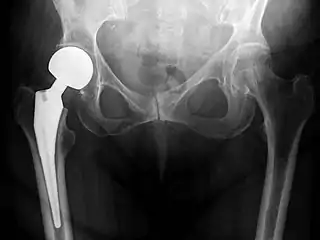

Post-operative projectional radiography is routinely performed to ensure proper configuration of hip prostheses.

The direction of the acetabular cup influences the range of motion of the leg, and also affects the risk of dislocation.[9] For this purpose, the acetabular inclination and the acetabular anteversion are measurements of cup angulation in the coronal plane and the sagittal plane, respectively.